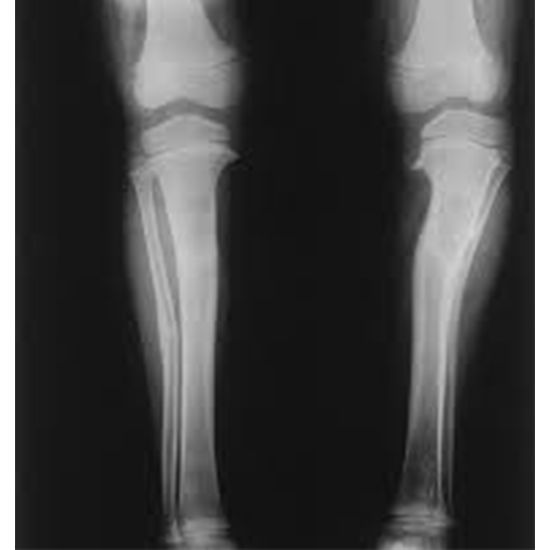

In a tibia and fibula, X-ray Test shows the lower leg bones (the tibia and fibula) and the soft tissues around them.

A tibia and fibula X-ray can assist clinicians in diagnosing lower leg pain, soreness, swelling, or deformity. It shows fractures. An X-ray can show if a damaged bone is aligned and has healed appropriately.

An X-ray can help surgeons plan and monitor the surgery. It can detect later-stage infections, cysts, tumours, and other disorders in the lower leg bones.